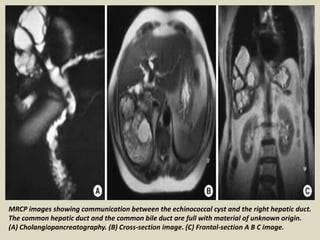

MRCP images showing communication between the echinococcal cyst and the right hepatic duct.

The common hepatic duct and the common bile duct are full with material of unknown origin.

(A) Cholangiopancreatography. (B) Cross-section image. (C) Frontal-section A B C image.